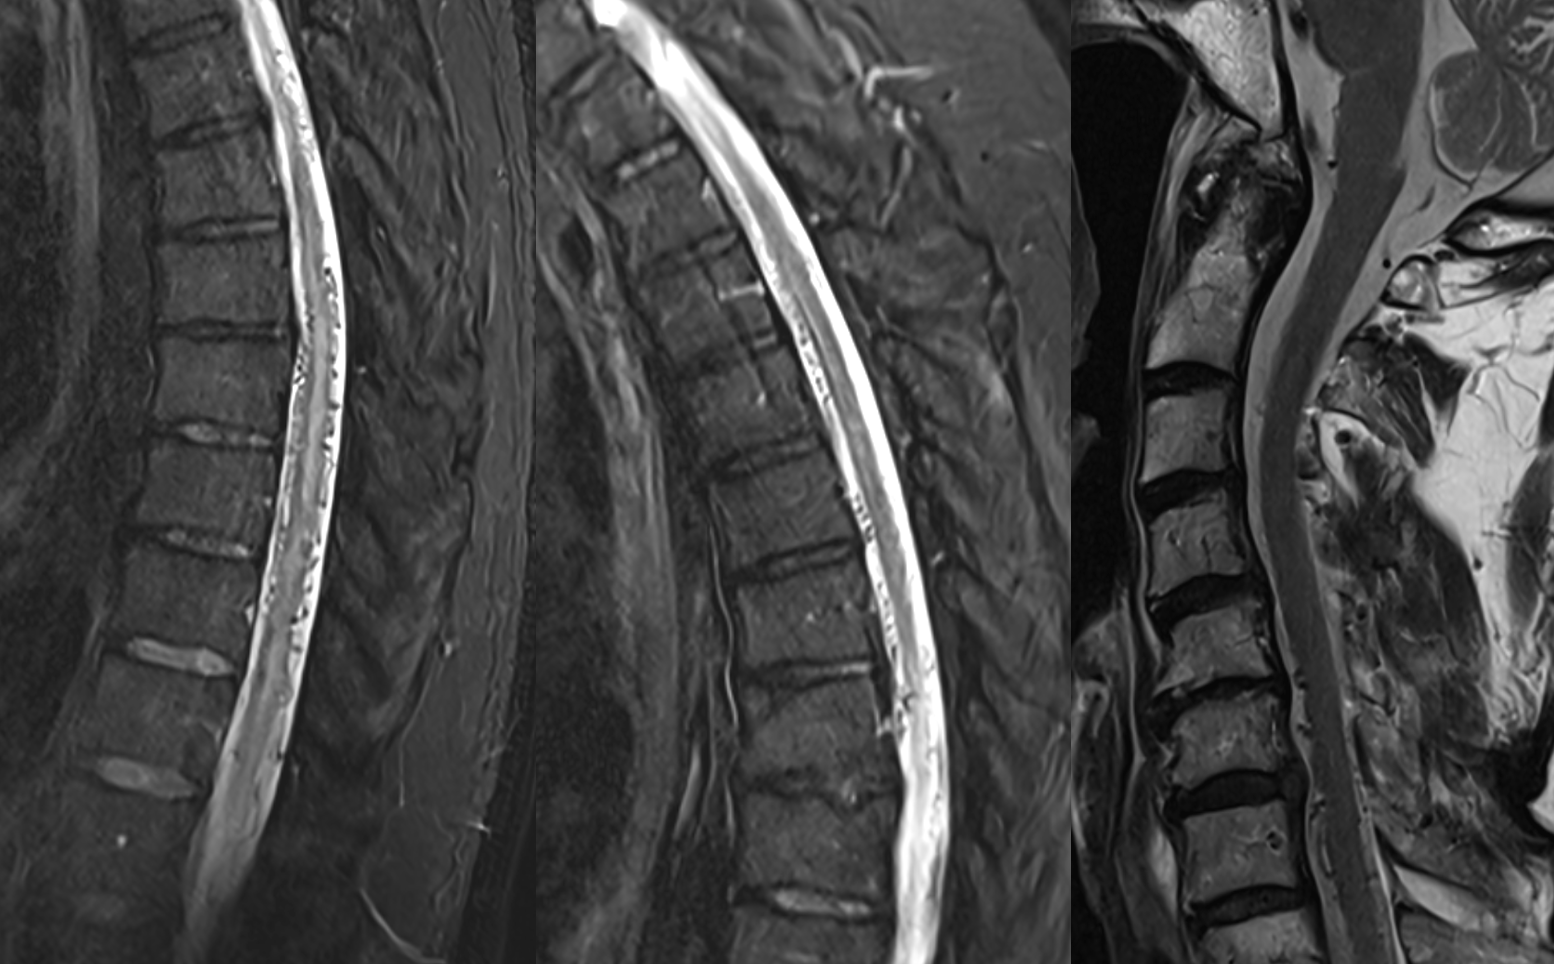

All dural fistula pathophysiology, and spinal too, consists of two key factors. One is fistula. The other is degree of venous congestion. Normal spinal venous anatomy consists of multiple radicular veins which drain the cord via nerve root sleeve / foramen into the epidural venous plexus. These veins are almost always deficient (missing from getgo, thrombosed, both?) in patients with spinal dural fistulas. Could it be that venous deficiency comes first, and fistula emerges later? Probably not, but interesting to consider. In any case, good spinal angiography involves imaging of fistula runoff to see extent of congestion and where drainage finally happens. In this case, there are no radicular veins in lumbar or thoracic cord at all. Not until the foramen magnum/C1/C2 do we see any outflow, and that is insufficient as well — with congestion extending all the way up to basal vein! Note perfect visualization of anterior pontomesencephalic and interpeduncular veins. When it finally reaches basal vein, the outflow is diluted by cranial venous tributaries.

In retrospect, corresponding veins on MRI and angio

It is critical to understand cord venous drainage in post-dural fistula patients is never normal. The radicular veins are still missing. This may in part be responsible for the incomplete clinical recovery, although the main reason is probably cord damage before fistula occlusion.